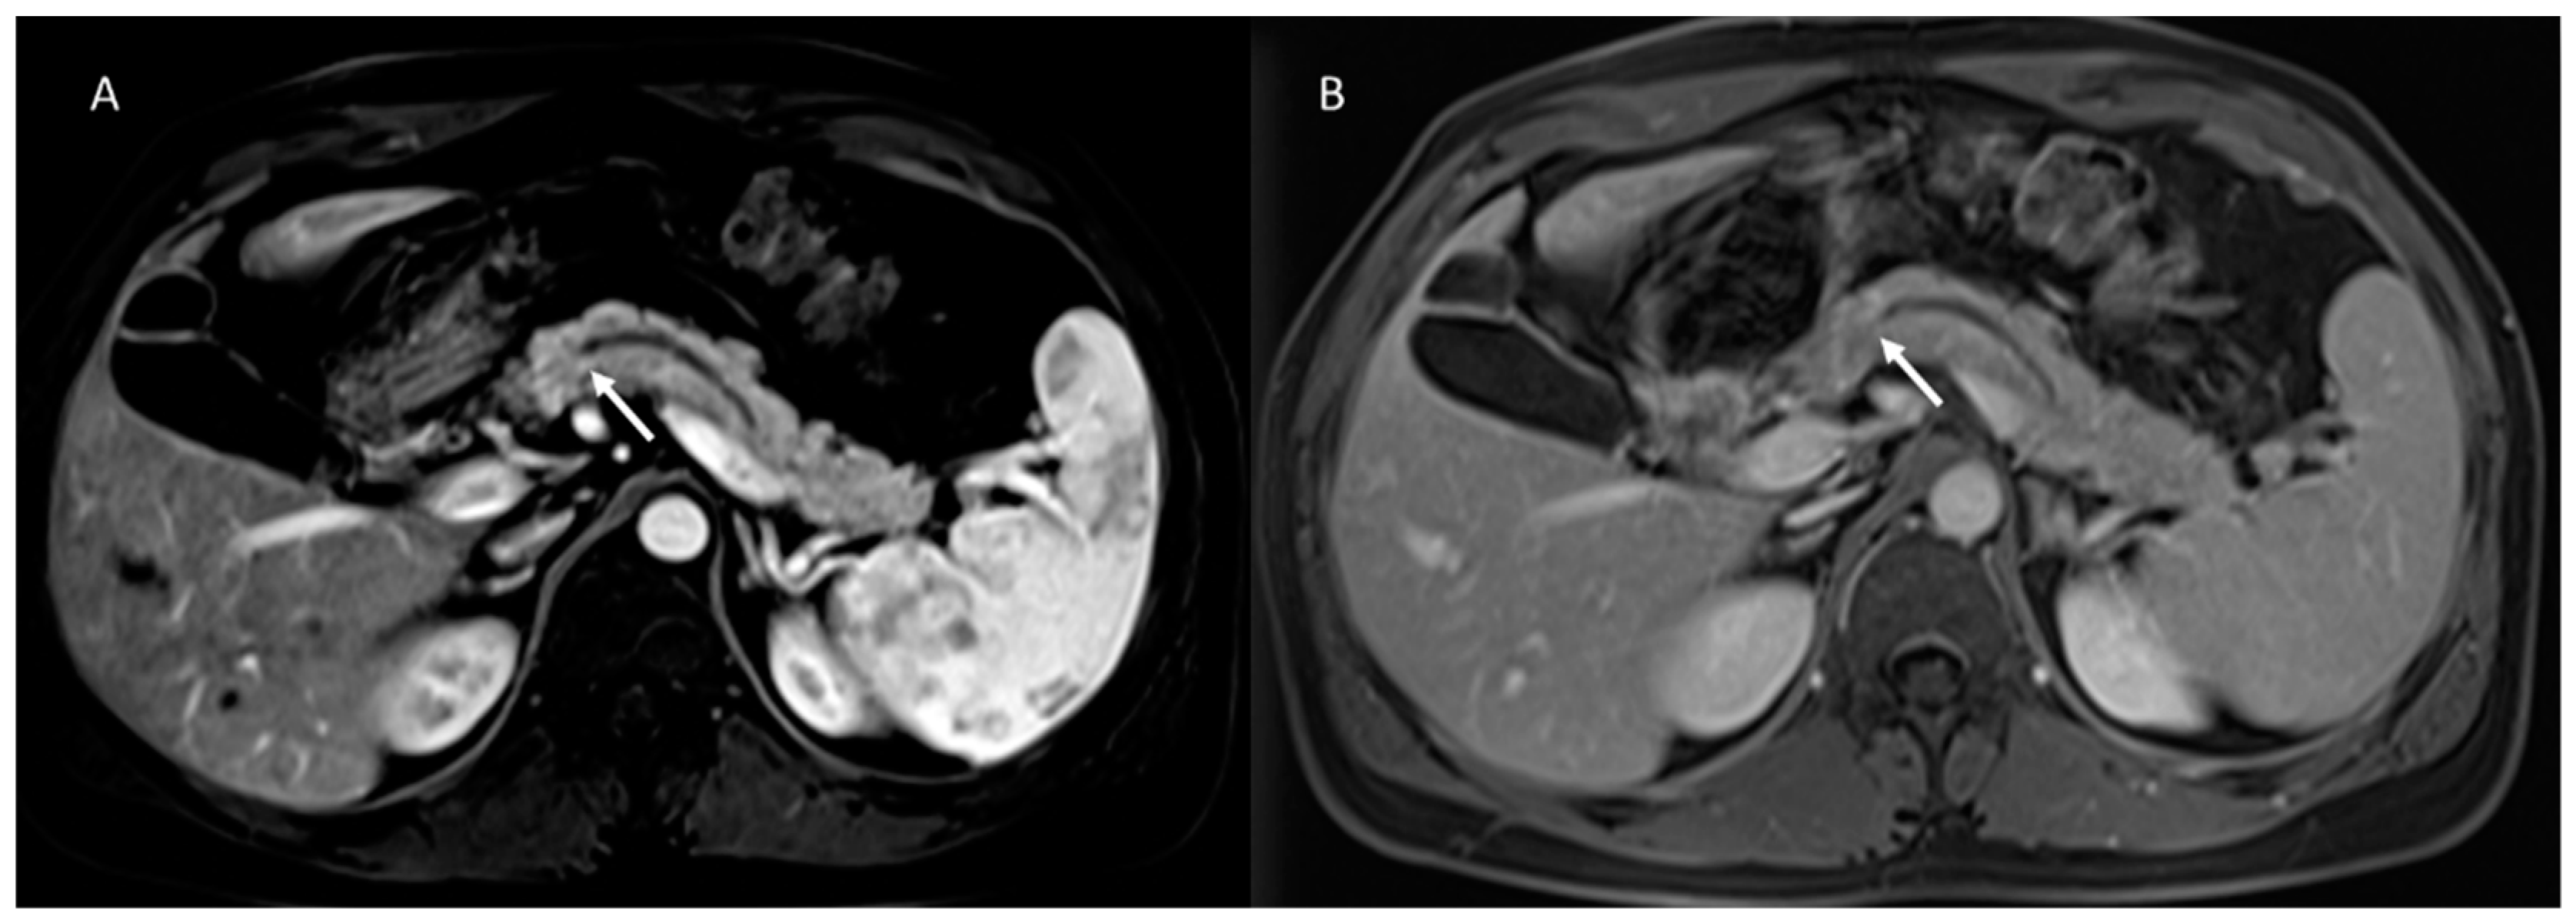

- Granata, V.; Fusco, R.; Sansone, M.; Grassi, R.; Maio, F.; Palaia, R.; Tatangelo, F.; Botti, G.; Grimm, R.; Curley, S.; et al. Magnetic resonance imaging in the assessment of pancreatic cancer with quantitative parameter extraction by means of dynamic contrast-enhanced magnetic resonance imaging, diffusion kurtosis imaging and intravoxel incoherent motion diffusion-weighted imaging. Ther. Adv. Gastroenterol. 2020, 13, 1756284819885052. [Google Scholar] [CrossRef]